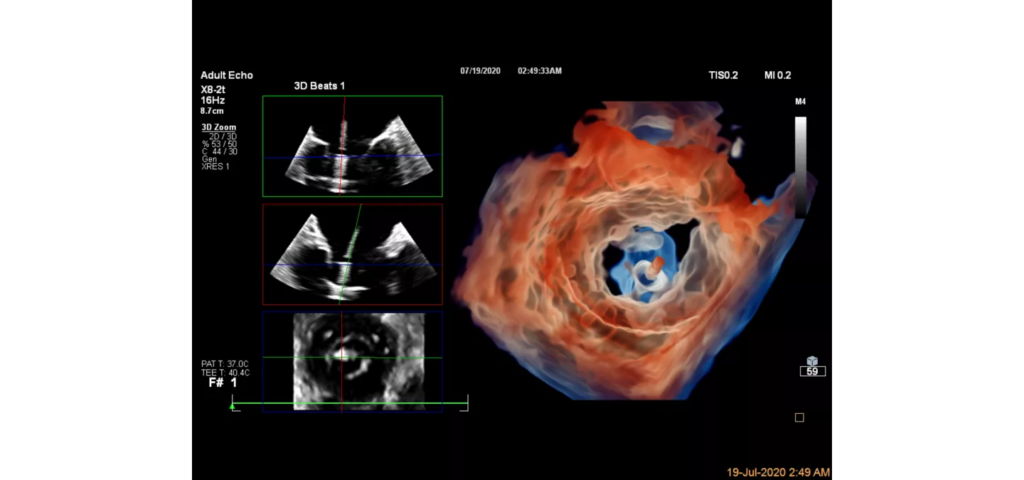

EPIQ CVx, our premium cardiovascular ultrasound system built on our innovative, modular, industry-leading ultrasound platform, has powerful AI-based capabilities and advanced diagnostic solutions to help you transcend today’s complexities and propel echocardiography into the next dimension. This enables you to achieve greater consistency, accessible innovation, smarter workflows, and easier scalability.

Epiq CVx